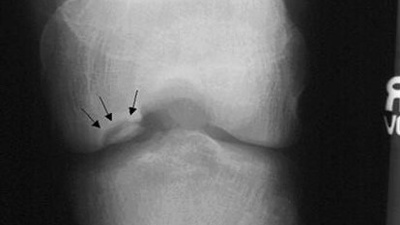

Хвороба Кеніга (розсікаючий остеохондрит колінного суглоба) – досить рідкісне захворювання, при якому розвивається обмежений остеонекроз ділянки субхондральної кістки, внаслідок чого відбувається дегенерація та відділення хрящової тканини в ділянці некрозу з подальшим зміщенням фрагмента